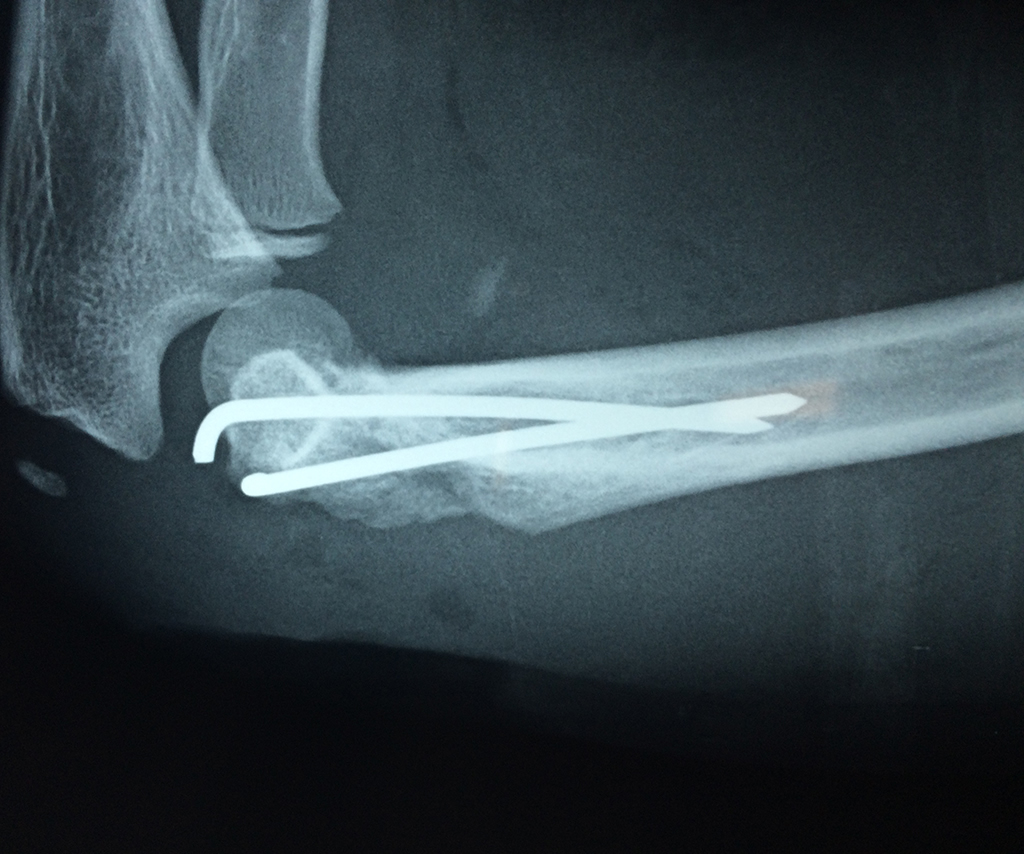

En anatomía humana, la articulación del codo es la que une el brazo con el antebrazo, conectando la parte distal del hueso húmero con los extremos proximales de los huesos cúbito y radio.

Por otra parte el cúbito y el radio forman también una articulación entre si en las proximidades del codo, la cual se denomina articulación radio-cubital proximal.